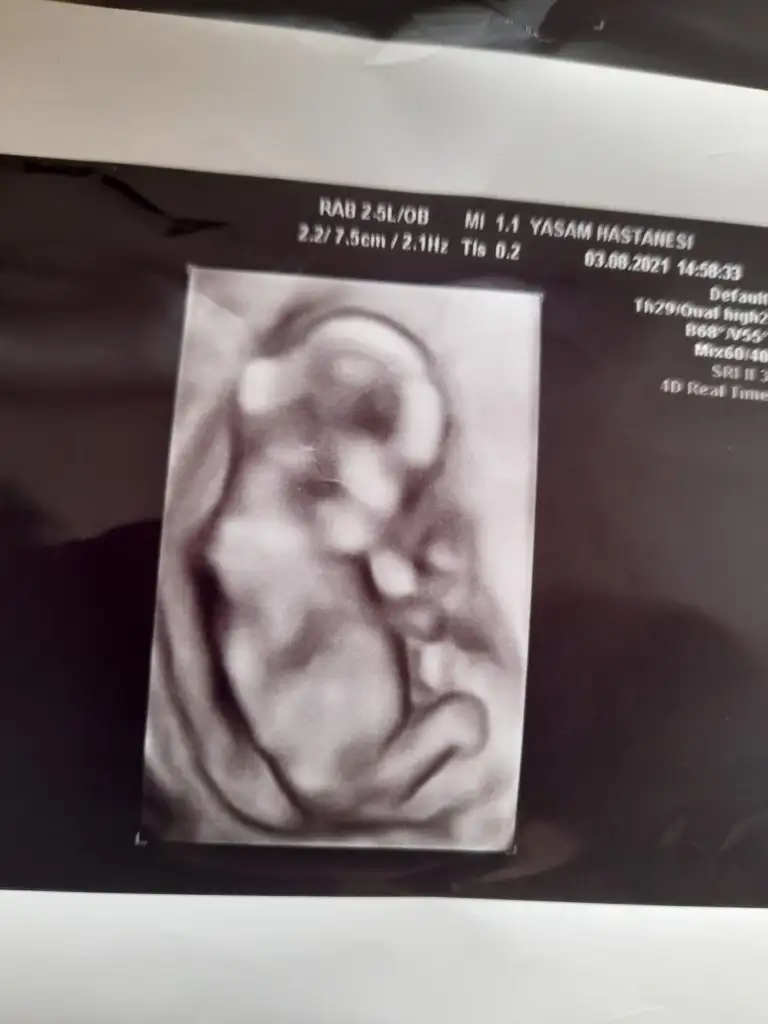

Bana da yorum yapabilir misiniz? İlk fotoğraf 6 haftalık 2 fotoğraf 9 haftalık keseye göre sizce cinsiyeti ne? :)